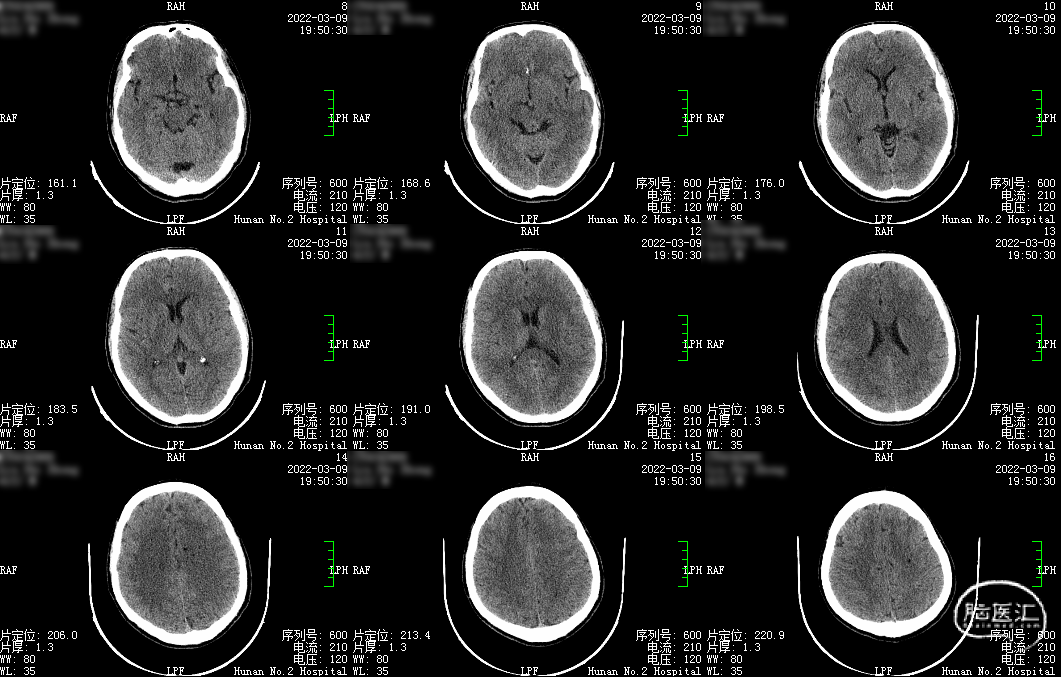

CT平扫(2022-03-09我院):

1.左侧半卵圆中心、双侧基底节区腔梗;2.脑内动脉多发钙化。